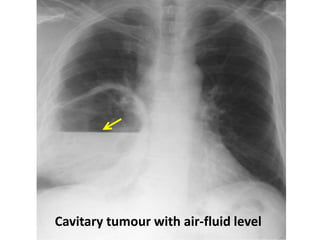

Cavitary tumour with air-fluid level

Cavitary lesion